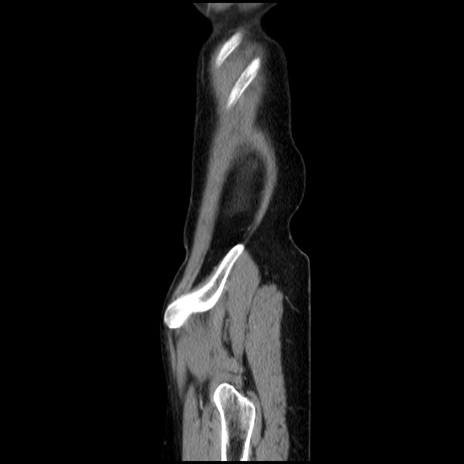

症例32(矢状断像)

【症例】40歳代 女性

【主訴】上腹部痛、嘔気・嘔吐

【現病歴】約9時間前頃から急に上腹部痛、嘔気、嘔吐が出現。改善しないため救急要請。

【既往歴】子宮頚癌(広汎子宮全摘術、放射線療法)、腸閉塞

【身体所見】腹部:平坦、軟、腸雑音亢進、上腹部を中心に腹部全体に圧痛あり。

【データ】WBC 8400、CRP 0.03